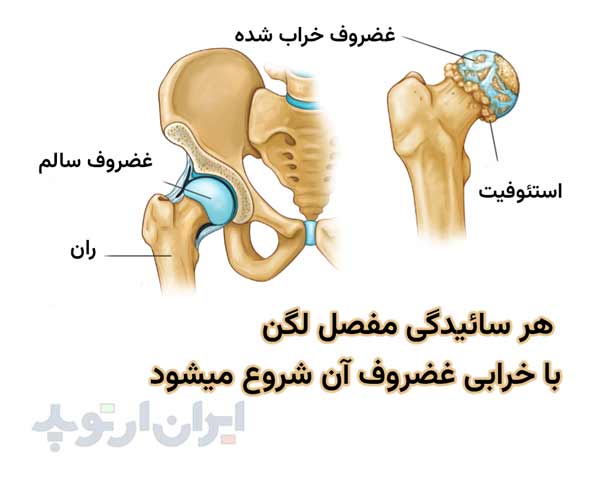

مفصل ران یا مفصل لگن یکی از مهمترین مفاصل بدن بوده و محل اتصال تنه و لگن به استخوان ران است.

مفصل ران وزن بدن را تحمل میکند. و نقش اصلی در هنگام راه رفتن با این مفصل است. خرابی مفصل ران موجب درد و لنگش و بد راه رفتن میشود.

مفصل ران ممکن است براثر بیماری های مختلفی مانند سیاه شدن استخوان لگن، روماتیسم، دررفتگی مادرزادی لگن یا شکستگی های لگن خراب شده و دردناک شود.

آرتروز یا ساییدگی مفصل

آرتروز یا ساییدگی لگن بیشتر در سنین بالا دیده میشود و ممکن است سابقه خانوادگی در ایجاد آن دخیل باشد.

در کسی که بطور مادرزادی استابولوم کم عمقی دارد ( به این بیماری دیسپلازی هیپ میگویند ) آرتروز لگن ممکن است در سنین جوانی ایجاد شود. هر زمانی که آرتروز شدید باشد، بیمار نیاز به انجام جراحی تعویض مفصل لگن خواهد داشت.